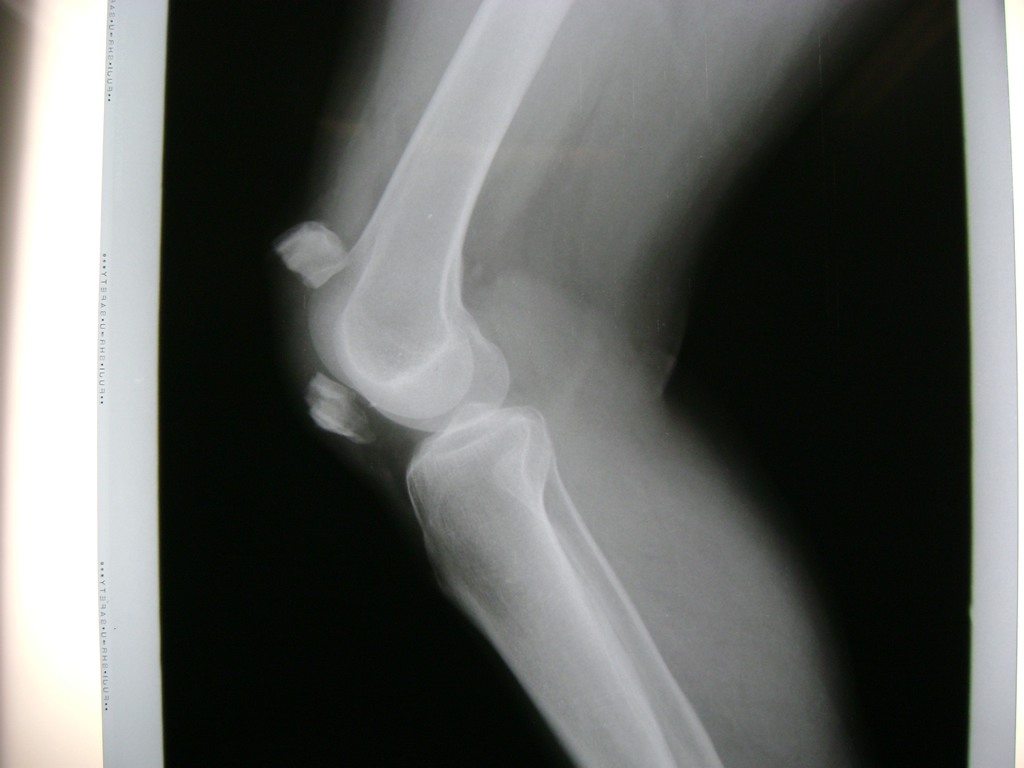

Cirugías de Rodillas

La artroscopia de rodilla es un cirugía en el cual la estructura interna de la articulación es examinada ya sea para realizar un diagnostico o para realizar un tratamiento, este procedimiento se realiza utilizando un instrumento parecido a un pequeño tubo llamado artroscopio.